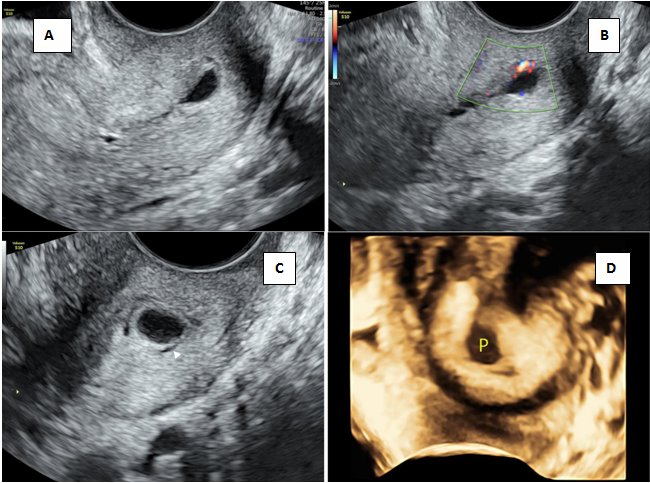

The important criteria for cervical pregnancy are the visualization of a gestational sac or trophoblastic mass below the level of the internal cervical os. In some cases the internal os is not clearly visualized due to increased endometrial thickness and echogenicity. In such cases a sac seen below the level of the uterine artery insertion itself can serve as a clue in finding cervical pregnancy as the uterine arteries insert at the level of internal os.2 If the gestation contains no sac or no living embryo, it is difficult to make a definitive diagnosis on a single U/S examination and needs a repeat evaluation. Sometimes, a small cervical polyp may mimic a sac and a case (Figure 3) referred as cervical pregnancy with a typical sac like structure in the cervical canal was actually a cervical polyp. Absence of the echogenic trophoblastic tissue surrounding the sac and vascularity in the pedicle of the polyp may help in the diagnosis. Early CP with its small ectopic size rarely presents with a typical hourglass shaped uterus. Besides, it is worth mentioning that the implantation site may occur in the high, middle, or low portion of the entire cervix, resulting in a varied location of sac along the cervical canal.15 Although fetoplacental remnants can be identified early in gestation with application of MRI, this tool remains inconvenient and limited due to its availability and high cost.16 Important diagnostic clue for a cervical pregnancy is that there would be a layer of healthy myometrium visible between the bladder and the gestation sac unlike caesarean scar pregnancy.17 Peritrophoblastic flow in CP which can be assessed using color flow Doppler is useful in both diagnosis and monitoring of treatment in cervical pregnancy.1,18–21

Figure 3 Cervical polyp mimicking low lying sac.

A) Transvaginal section of cervix showing sac like structure B) Eccentric vascularity seen in pedicle of polyp C) Polyp seen in the cervical canal with thin rim of fluid (arrowhead) D) 3D rendered image of polyp.